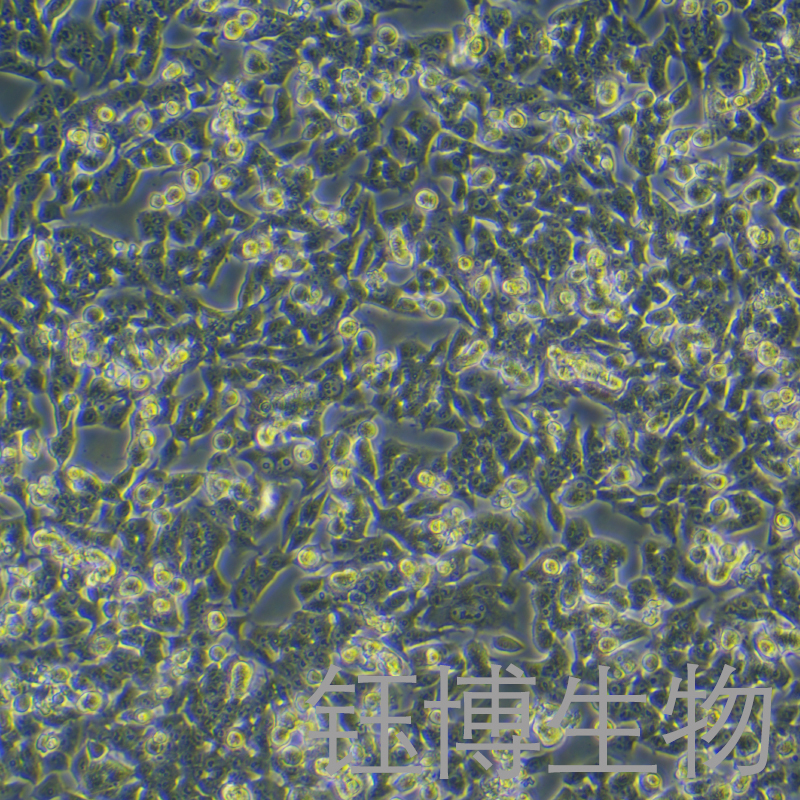

RM-1(小鼠前列腺癌细胞)

一、细胞基本属性

细胞名称

细胞别称

RM-1;小鼠前列腺癌细胞

细胞形态

上皮细胞样

背景简介

RM-1细胞是从17日龄C57BL/6胚胎泌尿生殖窦细胞感染Zipras/myc9逆转录病毒,移植于同基因成年雄性小鼠肾包膜下。